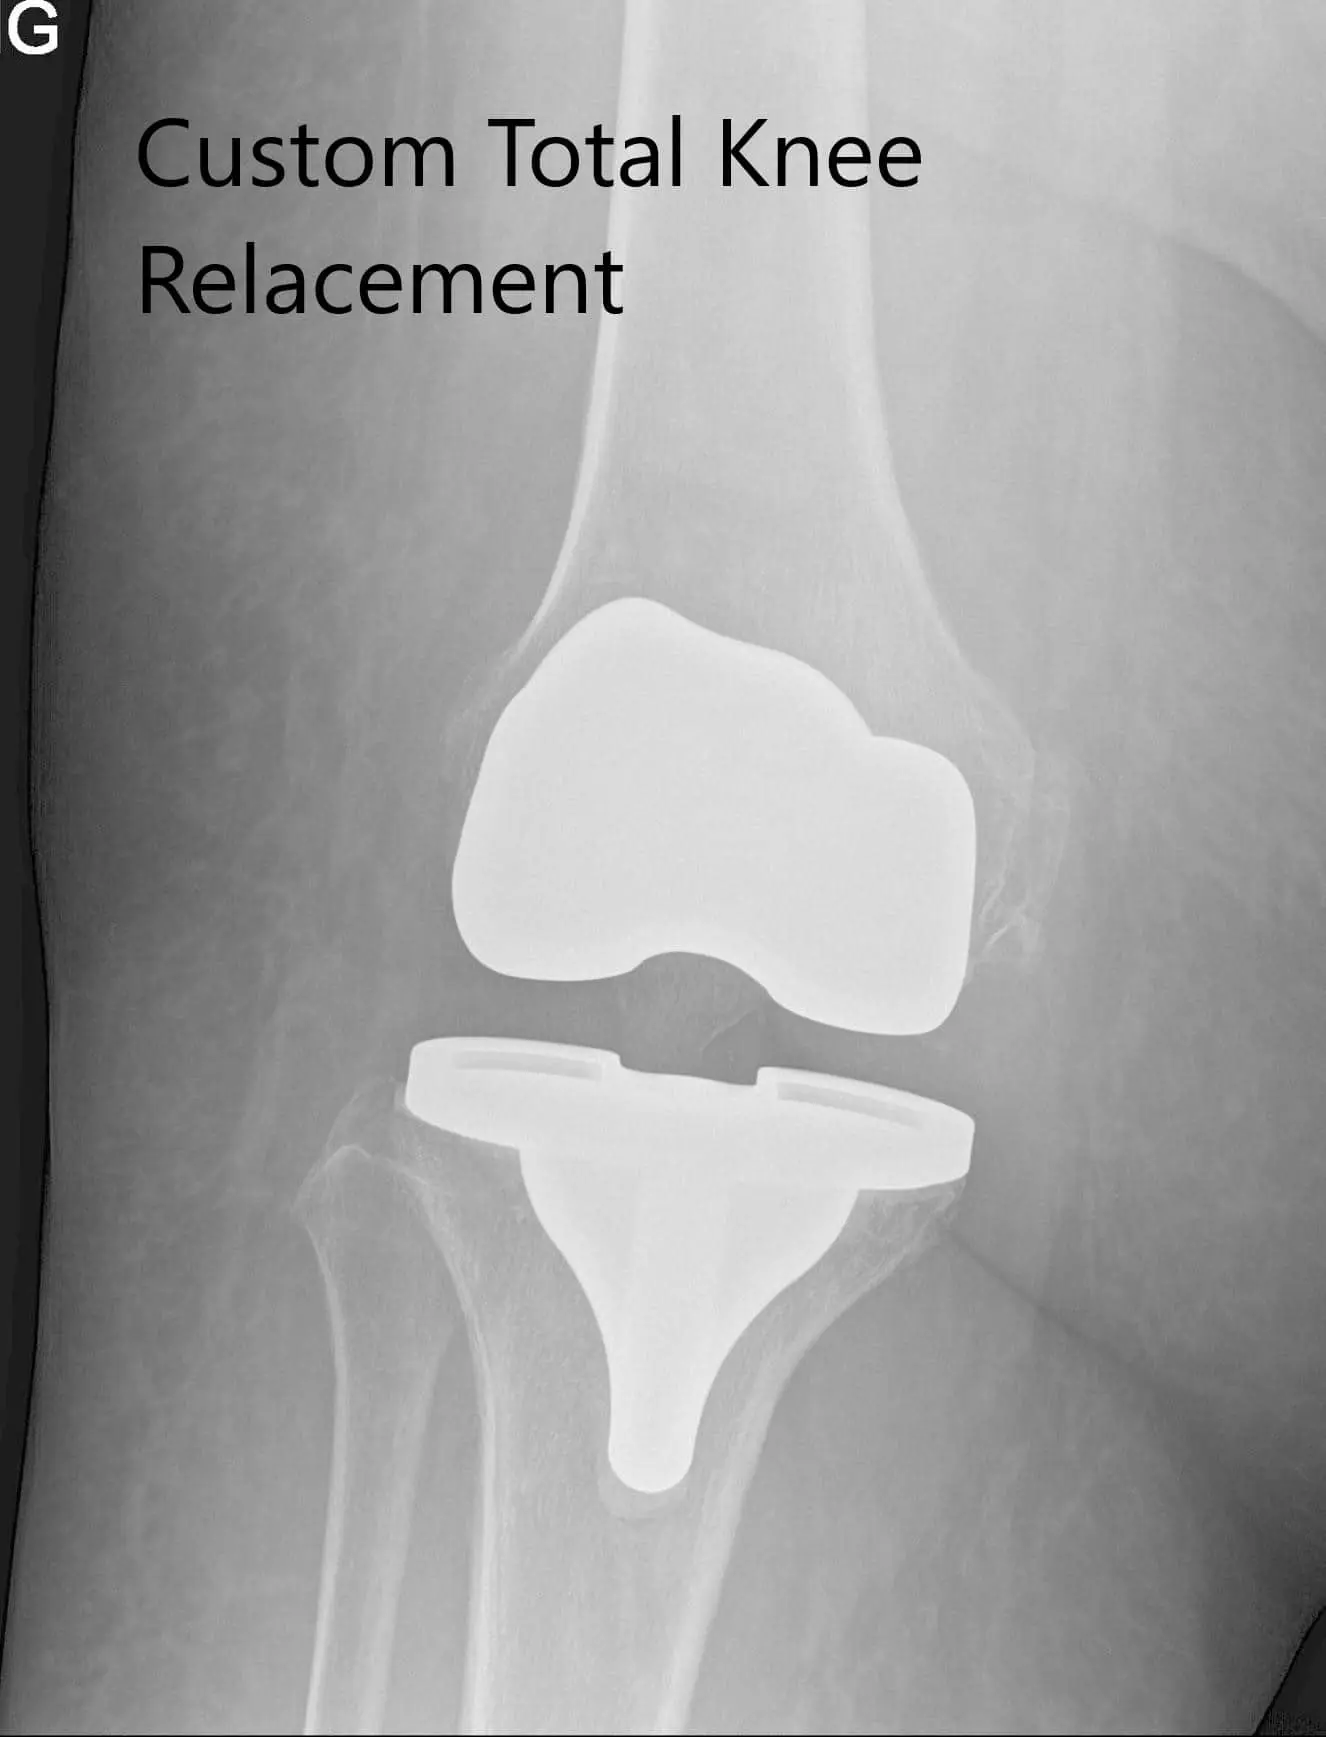

Postoperative x-ray images showing AP and lateral views of the right knee

Her postoperative x-ray demonstrated excellent alignment. Outpatient physical therapy was started for increasing the range of motion and strengthening of muscle. On a subsequent follow-up visit, she reported zero pain with a full range of motion. She was back to her baseline activities and expressed satisfaction at the outcome of the surgery. She follows up as needed.